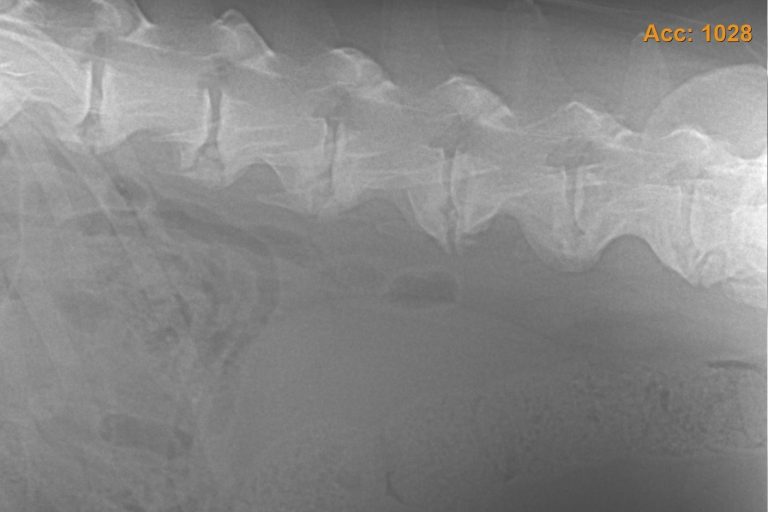

Physiotherapie

Hund & Pferd

Die Physiotherapie kann bei vielen Krankheiten unterstützend angewendet werden. Beispiele sind Post-OP, Arthrose, Arthritis, Fehlstellungen, Muskelatrophie, Dysplasien (ED, HD, OCD), Kreuzbandriss uvm. Zusätzlich kann sie als präventive Maßnahme, beispielsweise bei geriatrischen Patienten, sehr hilfreich sein.

Dorntherapie

Hund & Pferd

Die Dorntherapie ist eine manuelle, sanfte Wirbel- und Gelenktherapie, bei der mit Eigenbewegung des Hundes beziehungsweise des Pferdes das Skelett wieder in die Statik gebracht wird und Blockaden gelöst werden.